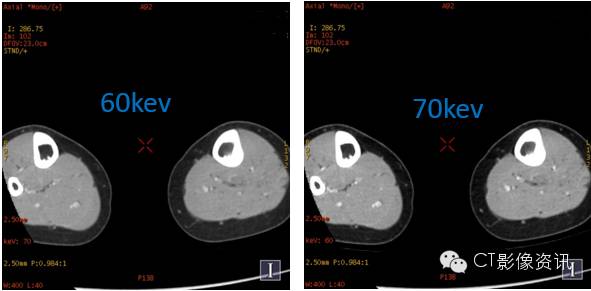

随着单能量水平的减低,左侧胫骨髓腔内的病变显示更加明显;低能量水平图像,可以很好显示小病灶以及轻微的强化病变。 左侧胫骨中段髓腔内转移